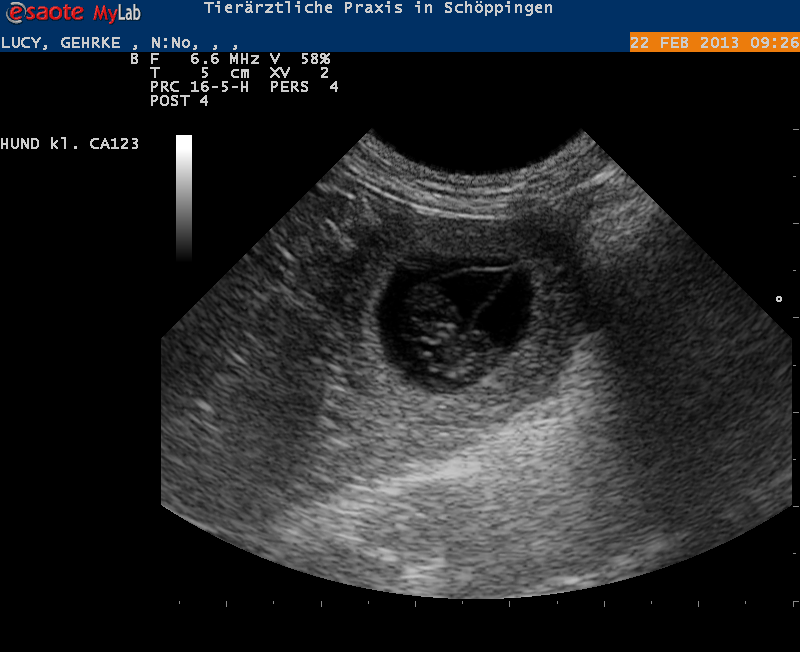

Freitag, 22. Februar 2013 - 12:33 Uhr

Lucy bekommt Welpen von Max das hat der Ultraschall heute morgen bestätigt

Ich freue mich und bin auch immer noch unendlich traurig, ich war heute morgen mit Lucy zum Ultraschall. Lucy ist trächtig von Max das wird der letzte Wurf von meinem Dreamboy!!! Das wird ein ganz besonderer Wurf

Gloris white and Black X Chelines Max Facttor

We expect Puppy´s That will be the last litter from my Dreamboy Chelines Max Facttor